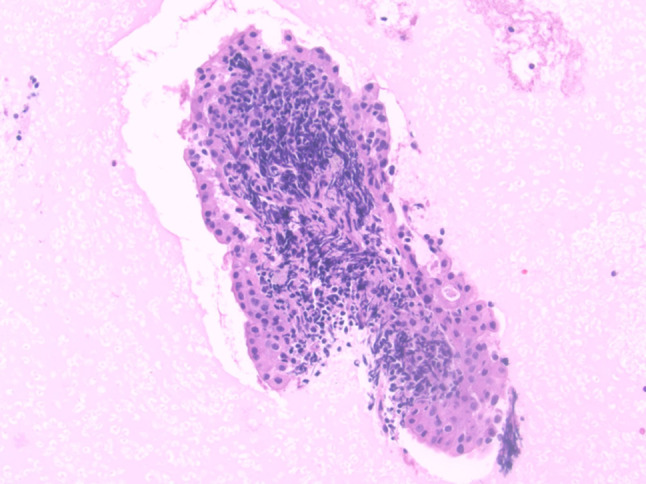

Fig. 8.

Cell block specimen showing a papillary fragment of a Warthin tumor with characteristic bilayered oncocytic epithelium and lymphoid-rich stroma (H&E stain, magnification × 20)